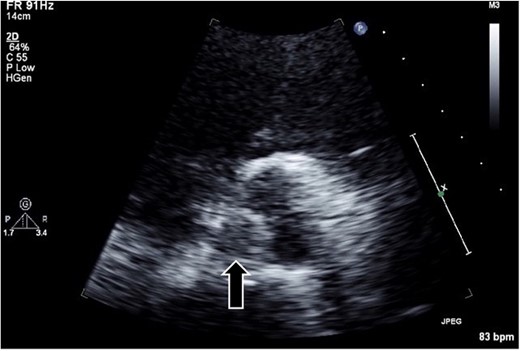

The surgical procedure employed a median sternotomy, with creation of cardiopulmonary bypass via cannulation of the ascending aorta and right atrium. After cross-clamping, cold antegrade cardioplegia was administered. Upon aortic valve exposure, a 2 × 2-cm vegetation was noted on the noncoronary cusp (Figs 2 and 3). The vegetation was quickly removed, and the noncoronary cusp was preserved. Following a 50-min bypass time, with a 35-min cross-clamp time, the patient was successfully weaned off bypass with minimal inotropic support. A portion of the vegetation was sent for culture; however, no bacterial or fungal growth was detected. Further histopathologic examination revealed a fibrin-rich thrombus containing red blood cells with organization at the periphery (Fig. 4).

Histopathological appearance of the vegetation: mainly fresh and organizing thrombus, consisting of fibroblast and capillary hyperplasia in the upper part of the specimen (hematoxylin and eosin staining, ×100).

NBTE frequently involves a systemic hypercoagulable state, including malignancy, systemic lupus erythematosus, antiphospholipid syndrome, polycythemia, and proteins C and S deficiencies [1–4]. The precise trigger for thrombus formation remains unclear. However, immune complex or mechanical endothelial injury sets in motion a cascade leading to platelet aggregate and fibrin strand deposition on cardiac structures [4, 5, 8]. Histologically, a fresh and organized thrombus, characterized by fibroblast and capillary hyperplasia, is observed within the vegetation adhering to the valve surface. Our case was diagnosed as NBTE on the basis of the abovementioned histological features; however, the cause of thrombus formation was not identified. Conversely, of note, vegetation developed in the aortic valve following CAG. As the right coronary artery originated from the left coronary apex, catheterizing the right coronary artery was difficult. Attempting multiple cannulations may have damaged the endocardium of the aortic valve. A previous case report showed aortic valve vegetation following radiofrequency catheter ablation of a left-sided accessory pathway via a retrograde approach [9]. Mechanical stimulation by the catheter may have induced thrombus formation.